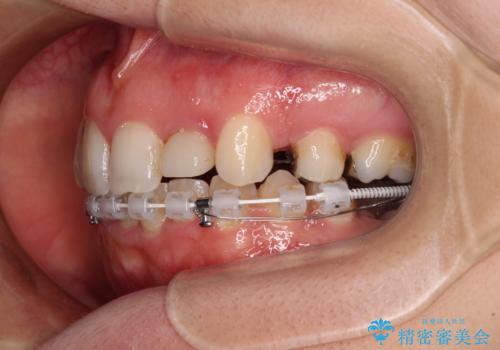

- 上顎前歯が叢生により前方に出ている状態や、全体的なむし歯を気にして来院された患者様です。

全体的にむし歯や欠損が多く、矯正治療とは別に処置が多く必要な口腔内でした。

口元の突出感を改善するために小臼歯4本を抜歯することとしましたが、左下は大臼歯が欠損していたため、そのスペースを活用し、小臼歯を3本抜歯して治療を行うこととしました。

目立たないハーフリンガル矯正を希望され、裏側装置はどうしても清掃性が低下し、むし歯発生のリスクが高まるため、矯正治療前にしっかりとむし歯治療を行い、矯正治療後にセラミックによる補綴治療を行うこととしました。

抜歯したスペースがなかなか閉じず、治療に時間はかかりましたが、術前術後のむし歯治療と合わせて3年10ヶ月で治療を終えることができました。